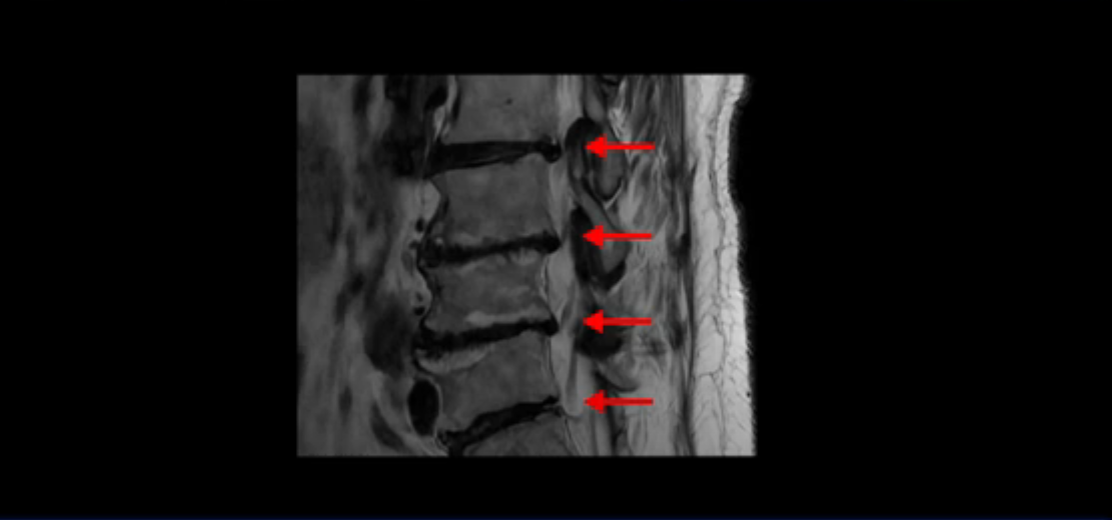

이 환자분 얘기 잘 들으셨습니까? 먼저 이분 MRI를 보면서 설명해드린 후 신경이 눌리는 협착증 환자분을 어떻게 수술 없이 치료할 수 있는지 자세히 설명 드리겠습니다.

보시다시피 이 환자분은 허리 여러 마디가 다 안 좋습니다. 4마디 디스크 높이가 심하게 주저 앉았습니다.

신경이 빠져나가는 추간공들이 좌우 다 좁아져 있고

척추관도 좁아져 있습니다.

이렇게 신경 구멍들이 좁아져 있어서 신경눌림 증상이 엉덩이와 다리에 생기는데, 이런 증상들은 근육과 매우 밀접한 관련이 있습니다.